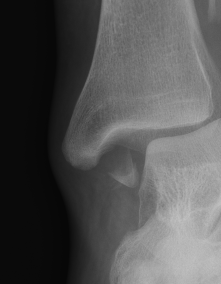

![]() |

Screw fixation

AO surgery reference medial malleolus lag screws